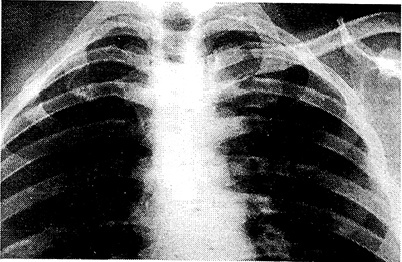

На обзорной рентгенограмме грудной клетки: легкие расправлены, жидкости в плевральных полостях не определяется, отсутствует тень лопатки и верхней конечности справа (рис. 1).

Рис. 1. Рентгенограмма больного Н. до операции.